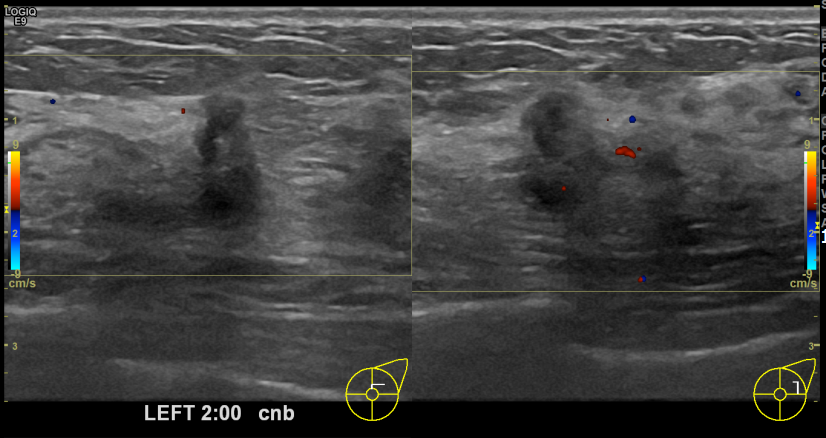

아산유외과개원후 726번째 유방암진단

상기환자 건진상 이상소견으로 조직검사권유받고 내원하신 30대 여성분으로 좌측유방멍울 조직검사시행후 유방암 진단되었습니다.